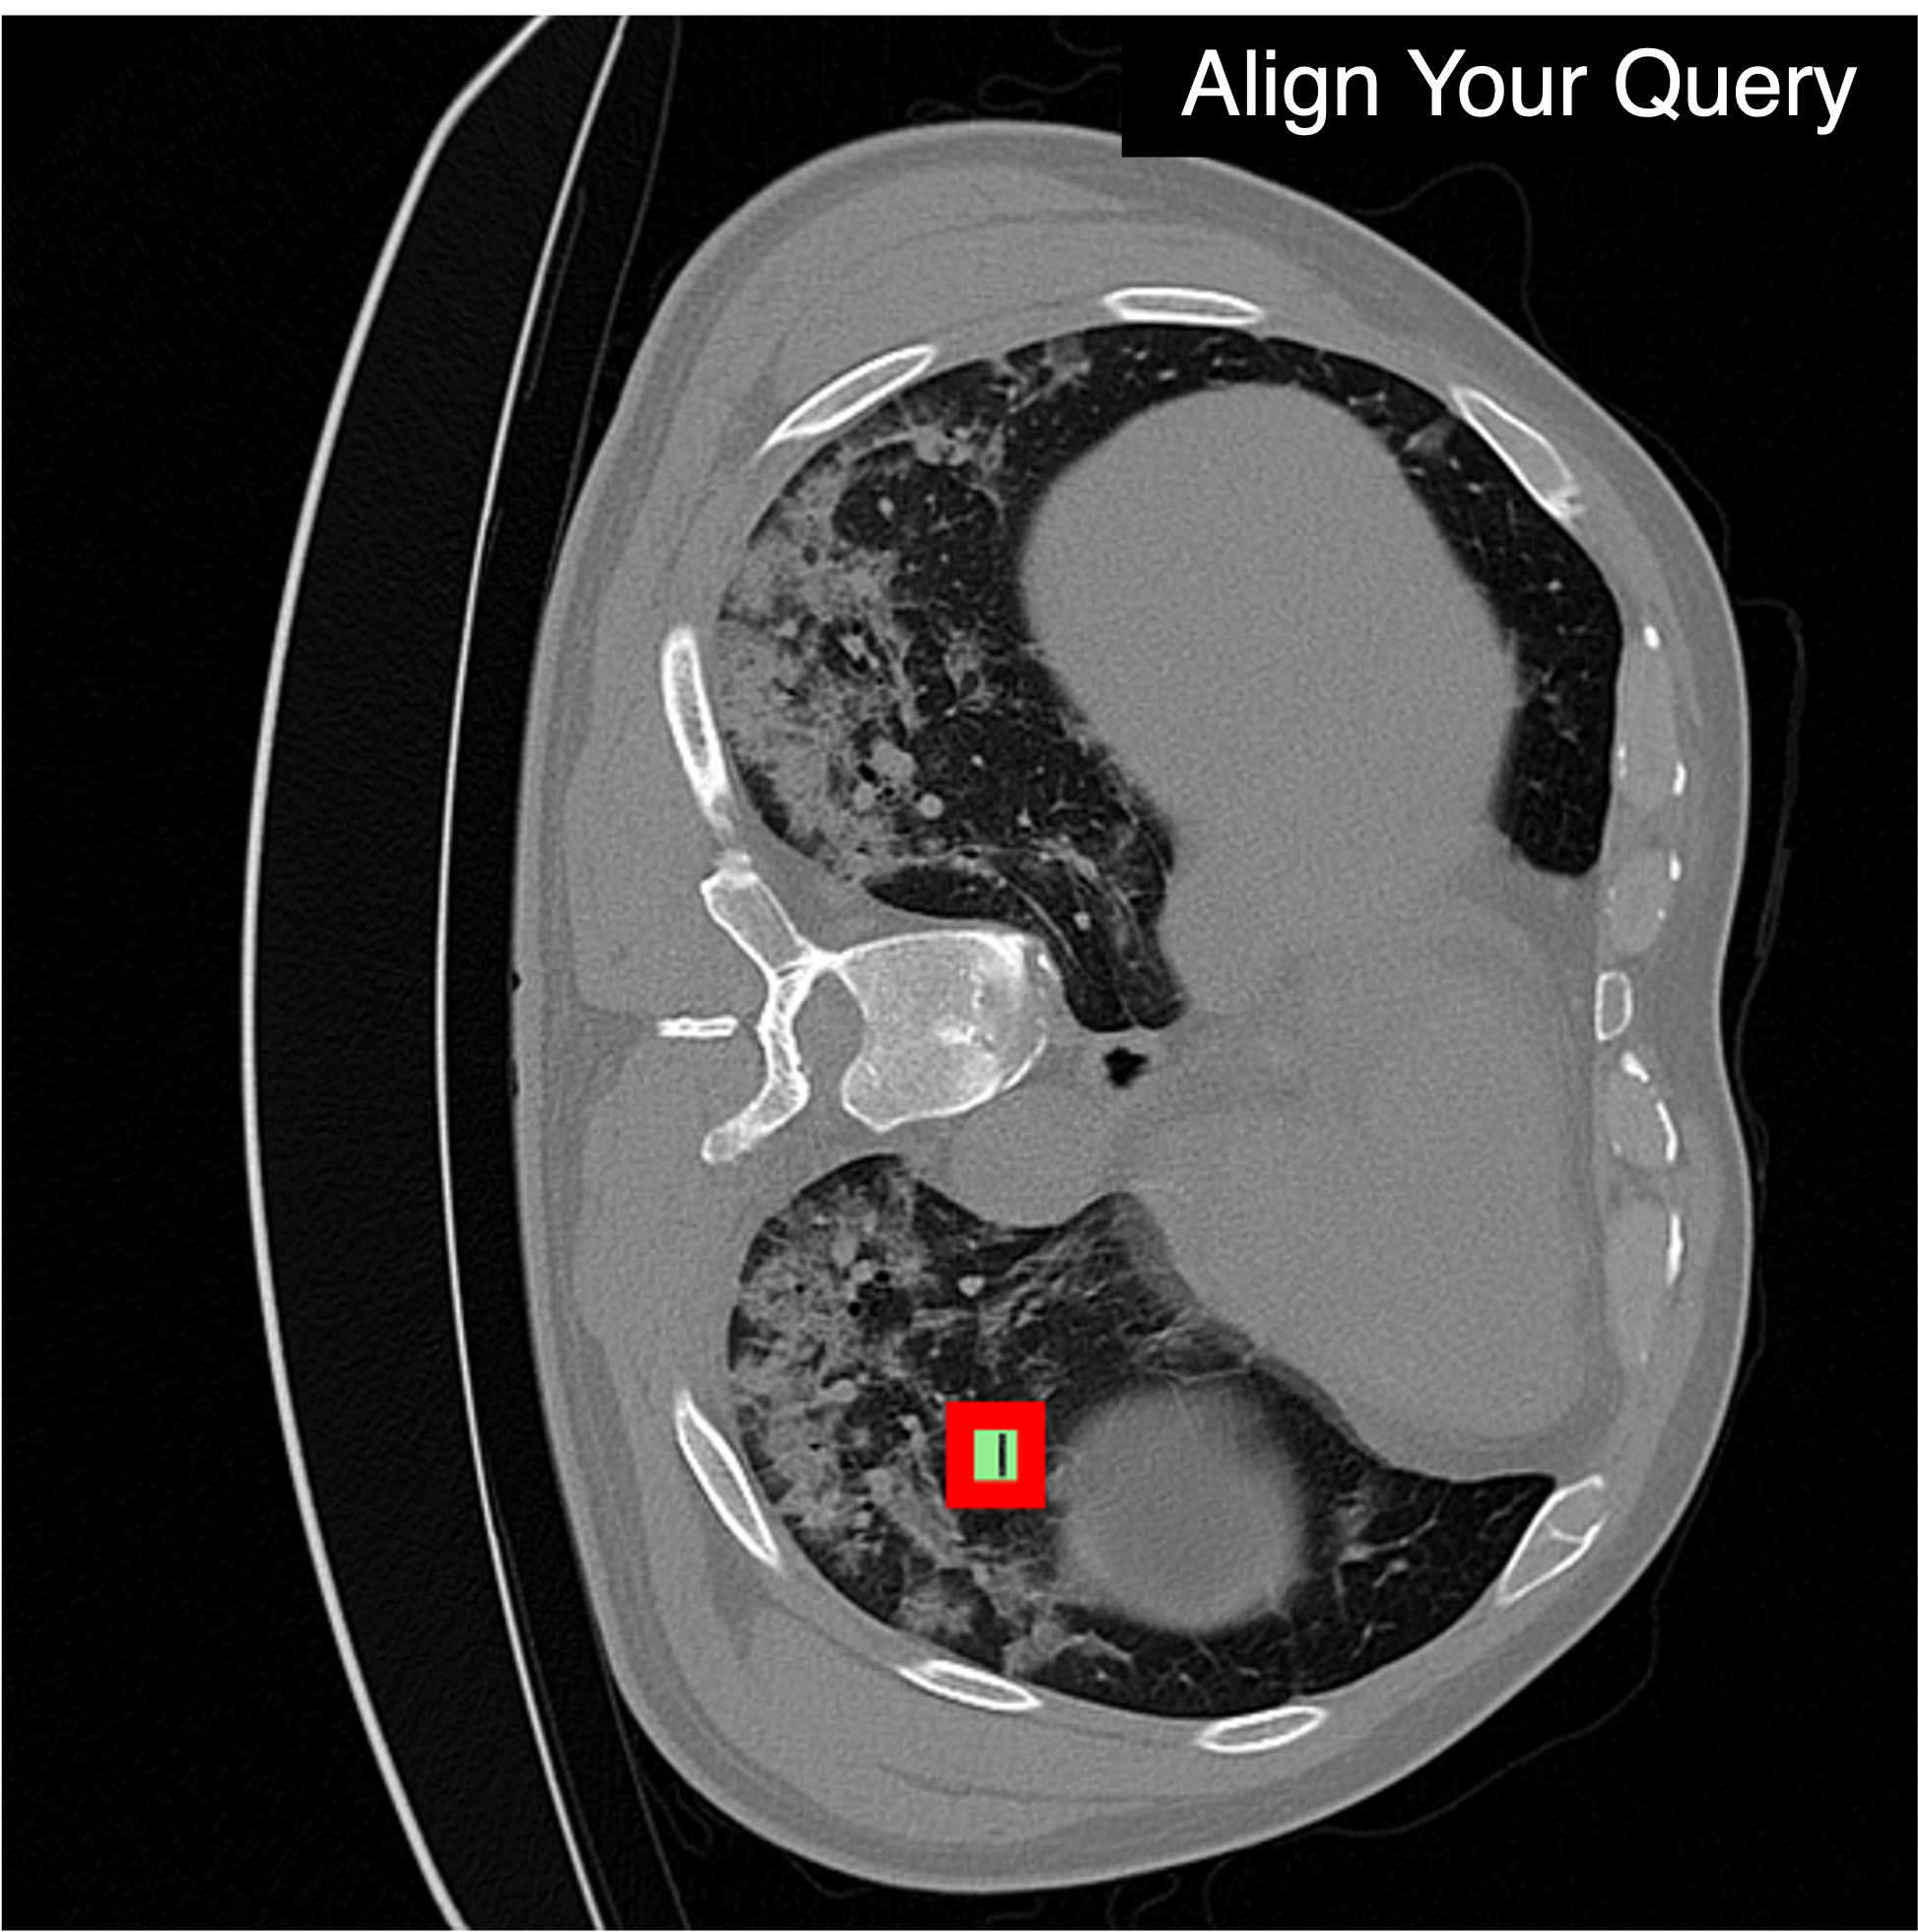

"COVID-19 infection in lung CT"

Qualitative Comparison. Comparison results between various state-of-the-art detection methods and the proposed method is shown above. Our method effectively leverages modality context to significantly enhance anomaly localization (red), compared to baseline results (blue). Ground truth bounding boxes are green. For cases where the bounding boxes are small, insets show an enlarged view of the highlighted yellow region.